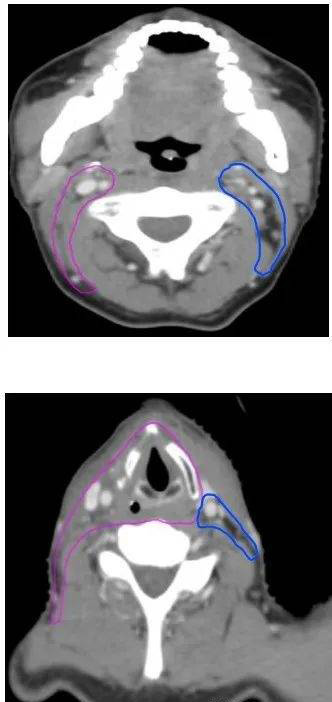

病例一:根治性放疗(下咽鳞癌T2N2bM0 IVA期,左侧梨状窝)

GTVp为肿瘤原发灶(由喉镜和CT、MRI、PET/CT等检查共同确定)

GTVn为阳性淋巴结(由CT、MRI、PET/CT等检查共同确定)

CTV1为高危亚临床病灶(包括左侧梨状窝原发灶、阳性淋巴结、同侧咽后及同侧淋巴引流区II-V区,全喉及相邻会厌前)

CTV2为低危亚临床病灶(包括对侧咽后及淋巴引流区II-IV区)